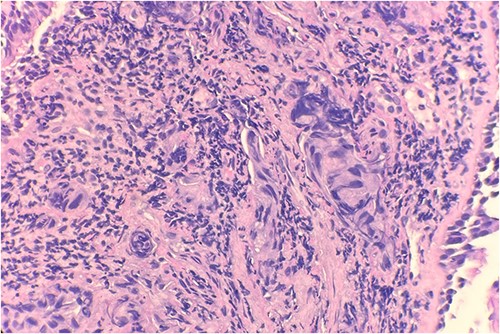

Pathology evaluation from the right middle lobe biopsy showed few clusters of malignant cells, consistent with ADC (Fig. 1). Immunohistochemical staining showed tumor cells were positive for AE1/3, Napsin A and TTF1 (Fig. 2), with ⁓60% Ki-67 positivity. Tumor cells were also negative for CK7 (Fig. 3), p40, p63, CK20 and CK5/6. The overall tumor morphology features and immunoprofile favored moderately differentiated ADC of the lung. However, other primary sites could not be ruled out.

Tumor cells are positive for TTF1 by immunohistochemical stain (IHC) 20×.